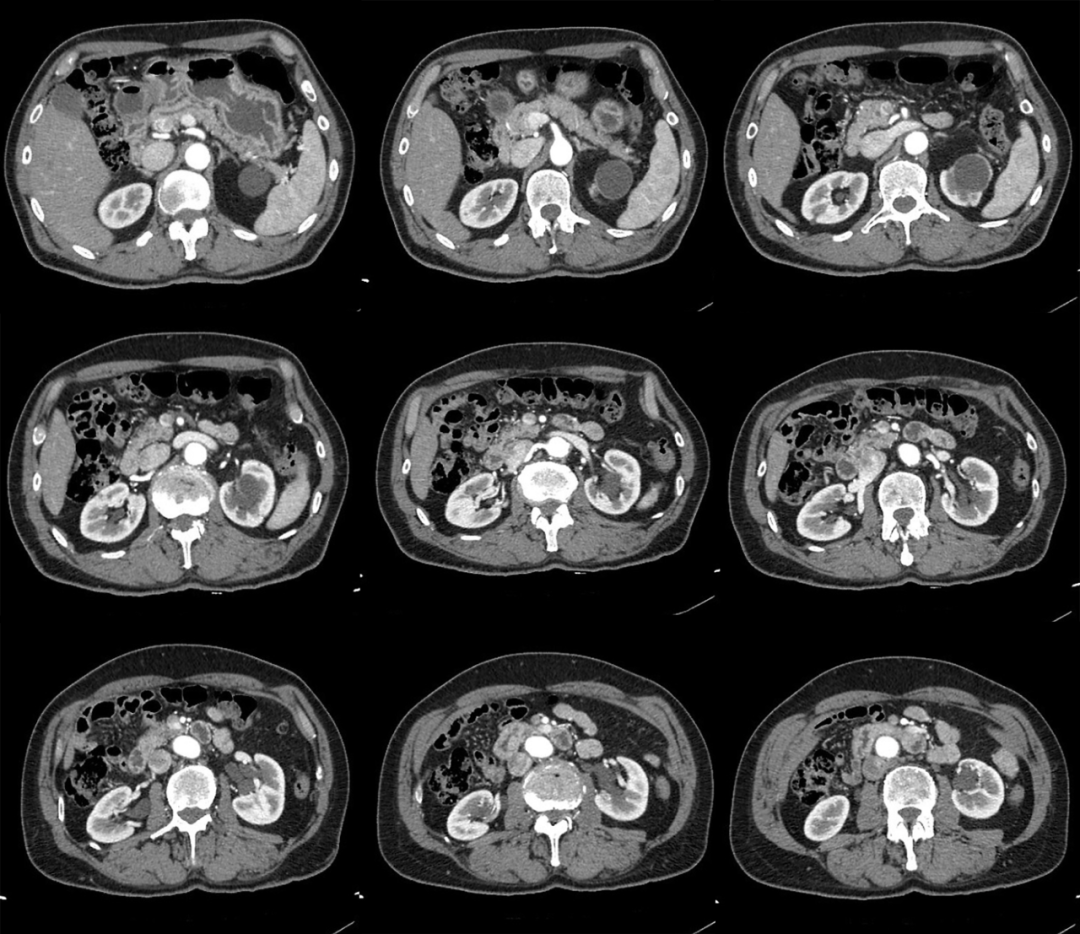

虽然超声是评估肾囊性病灶的首选检查,但大多数的肾盏憩室超声分辨不出。增强 CT 延迟期扫描在诊断肾盏憩室的敏感性为 95%,另一方面,磁共振 (MRI) 尿路水成像也成为一种有价值的检查方法,MRU 尿路造影技术,使用各种 T2 加权序列,将尿路视为静态液体柱,不需要打造影剂。

2、肾盏憩室主要表现为:肾内囊性占位,平扫时囊性灶与肾盏分界不清,增强后造影剂进入囊肿(主要在延迟期造影剂进入憩室内);有时囊肿内可以看到结石或者钙乳样沉积物;肾盏憩室病灶主要偏向外周生长。